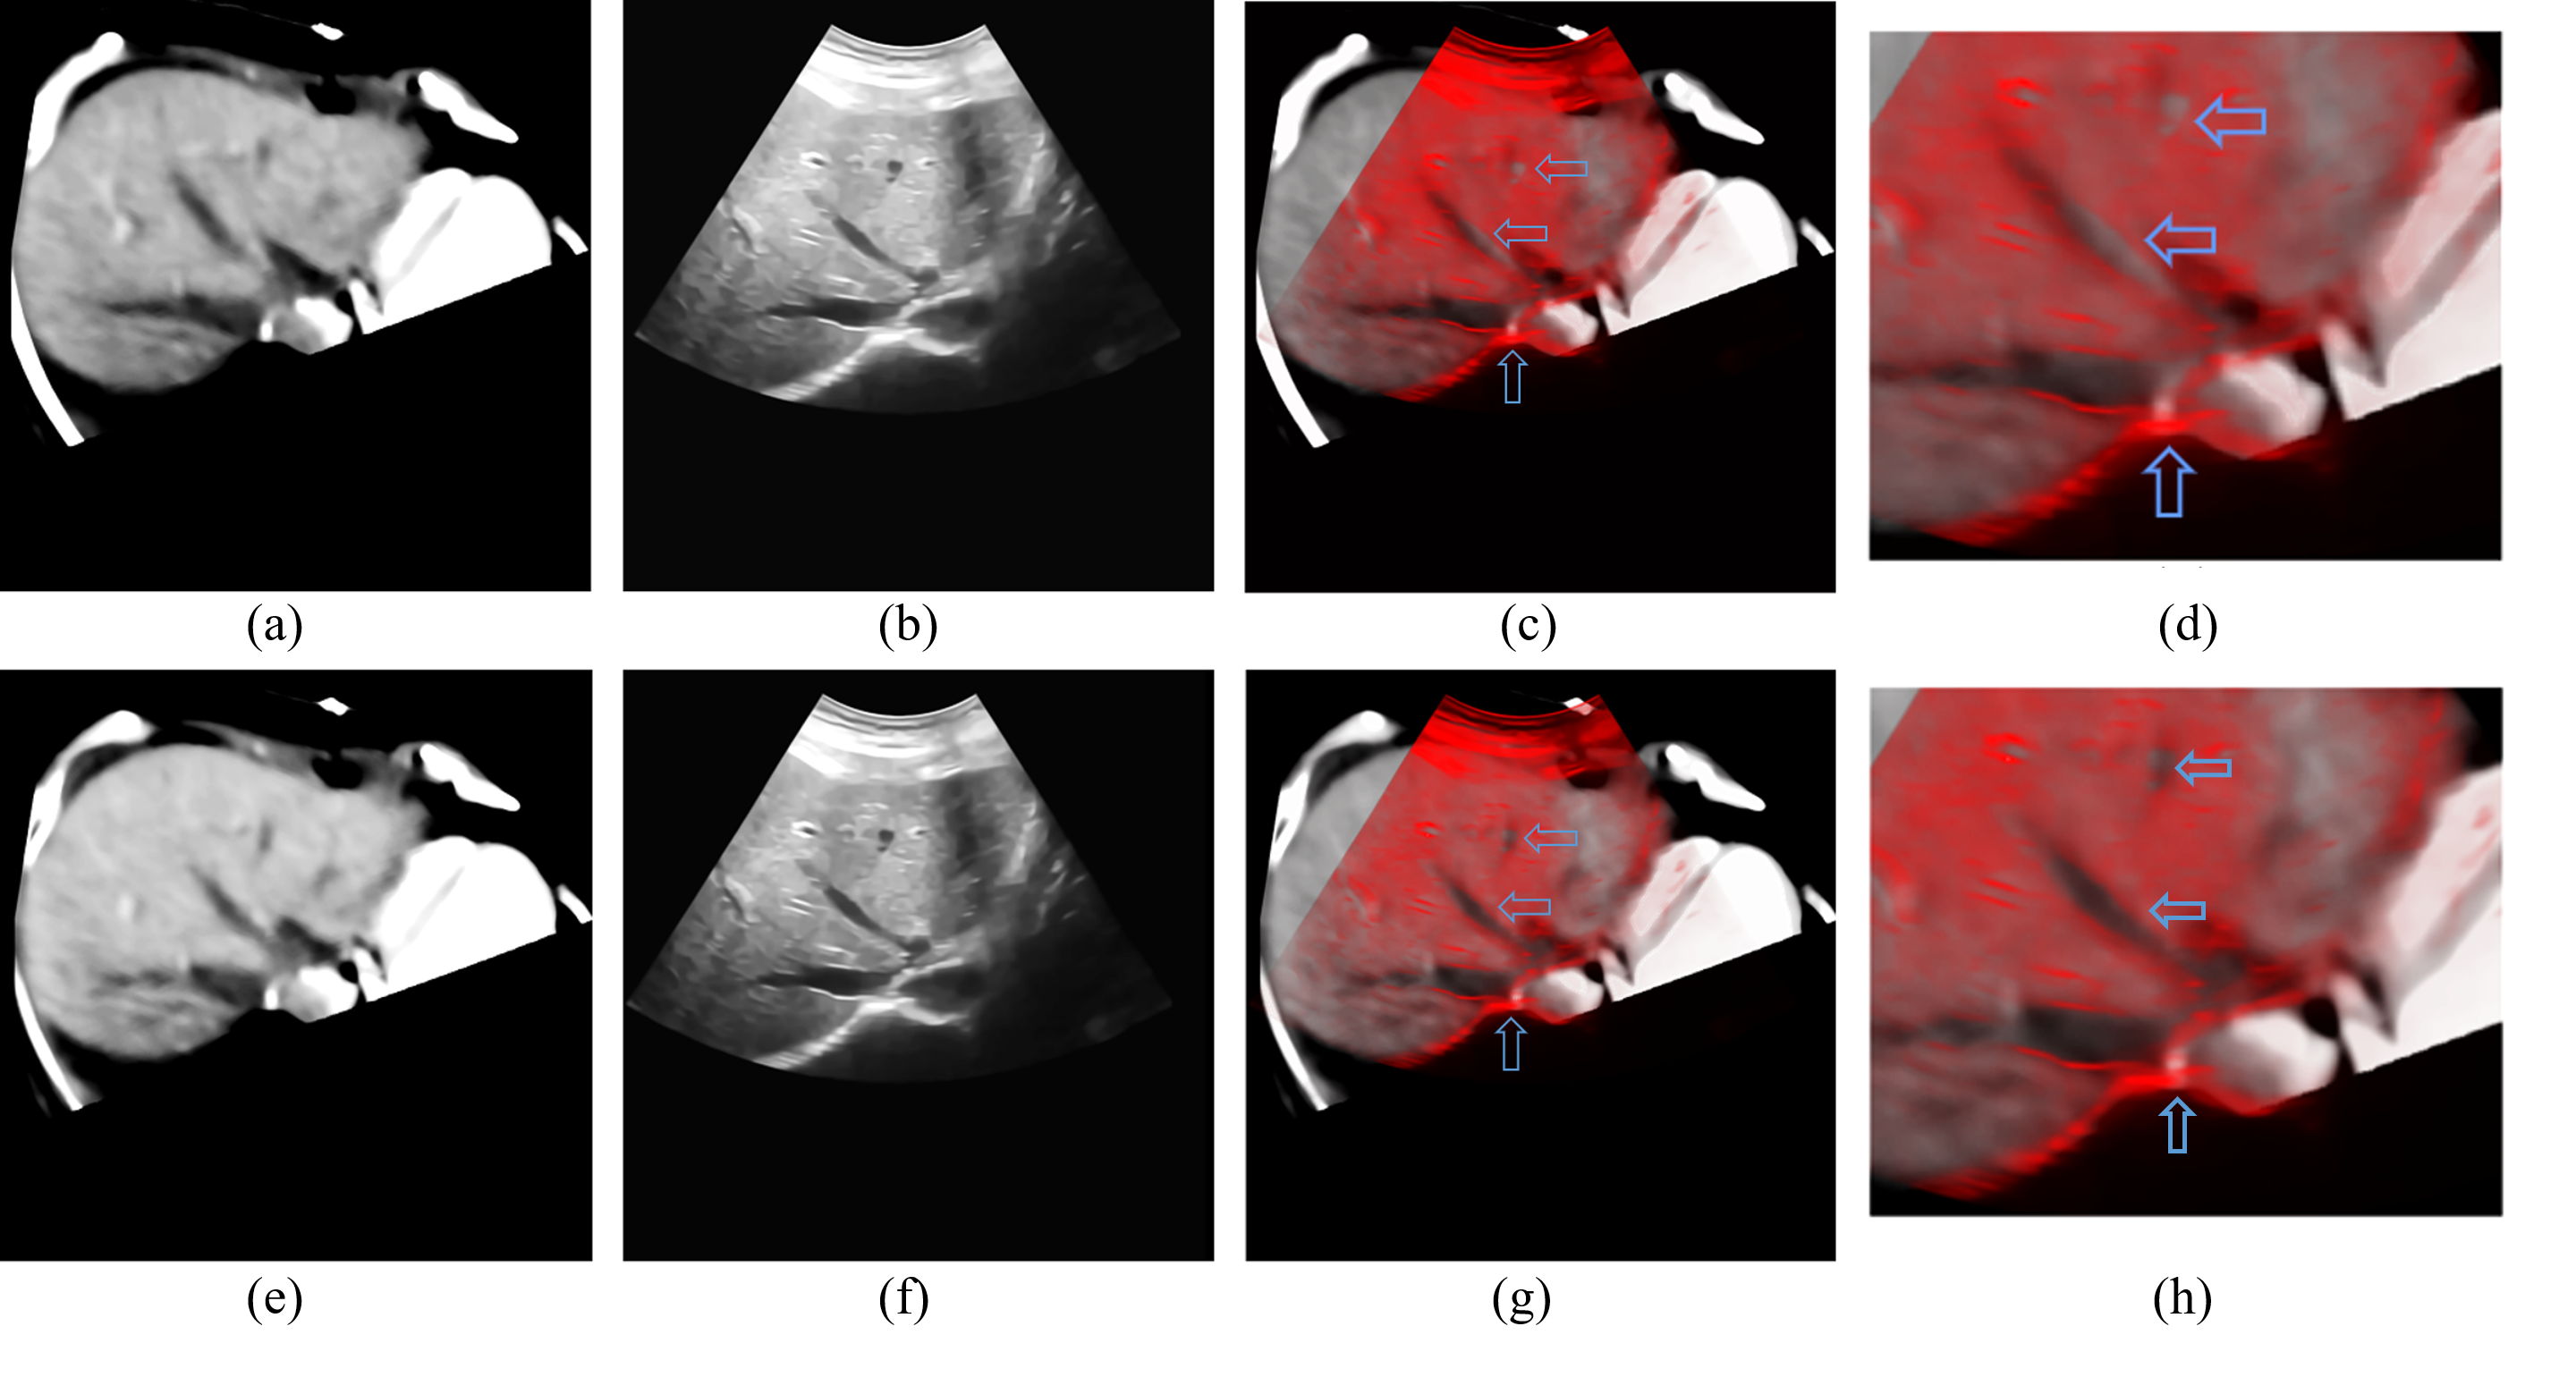

Refer to caption

Figure 5: The data before and after registration of test 3. (a) is the corresponding CT slice of the original ultrasonic image (b) after the matching of world coordinate system. (e) is the result of the rigid registration from CT volume data to ultrasonic image. (f) is the non-rigid registration result of the ultrasonic image (b). (c) and (g) are the fusion image of (a) (b) and (e) (f), (d) and (h) are the details of (c) and (g), respectively.

The data before and after the registration are shown in Fig. 3-5, where subfigures 3(a), 4(a) and 5(a) are CT slices corresponding to original ultrasonic images, subfigures 3(b), 4(b) and 5(b) after the matching of the world coordinate system. Subfigures 3(e), 4(e) and 5(e) are CT slices after rigid registration to original ultrasonic images, and subfigures 3(f), 4(f) and 5(f) are non-rigid registration results of original ultrasonic images to their correspondence rigid registered CT slices. And fusion images of CT slices and ultrasonic images before and after registration are obtained and shown in Figs. 3(c) – 5(c) and 3(f) – 5(f) to better evaluate our algorithm. According to these figures, on comparison with the fusion image before registration, boundaries of both the liver and vessels are better matched. And the positions and shapes of vessels are also corrected. And the positions of bones in Figs. 4(g) and 5(g) are also closer to their positions in the ultrasonic images, which can be inferred by their “shadows” in the ultrasonic image.

The details of results in Figs. 3-5 are shown in subfigures (g) and (h) of Figs. 3-5, which also show that our registration algorithm can improve the matching accuracy between the CT data and ultrasonic images, especially in the parts pointed by arrows in Figs. 3 and 4. However, although our algorithm has better registration performances than the Demons algorithm, there still exists some parts that can be improved, such as the places pointed by the blue arrow in Fig. 4(h) although the distance between points A2 and B2 is shorter than that between points A1 and B1, points A2 and B2 are still not matched.